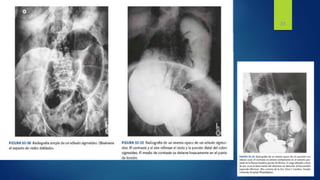

Las radiografías del abdomen

• revelan un colon sigmoide muy dilatado

que recuerda a una tubería doblada, con su

vértice en el cuadrante superior derecho.

• Puede observarse un nivel hidroaéreo en el

asa de colon dilatada

Un enema de contraste

• el punto de obstrucción con la deformidad

en pico de ave patognomónica que revela

la torsión que obstruye la luz sigmoidea.